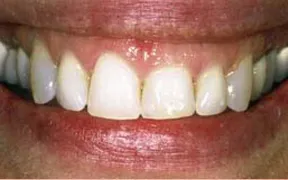

Periodontal Gallery Case 3

This is another case of a gummy smile. The gum tissue covered up too much of the teeth, which caused them to look short.

A crown lengthening procedure was performed, which evened the height of the gum tissue across the front teeth. This type of procedure typically leads to patients smiling with more confidence... and much more often!